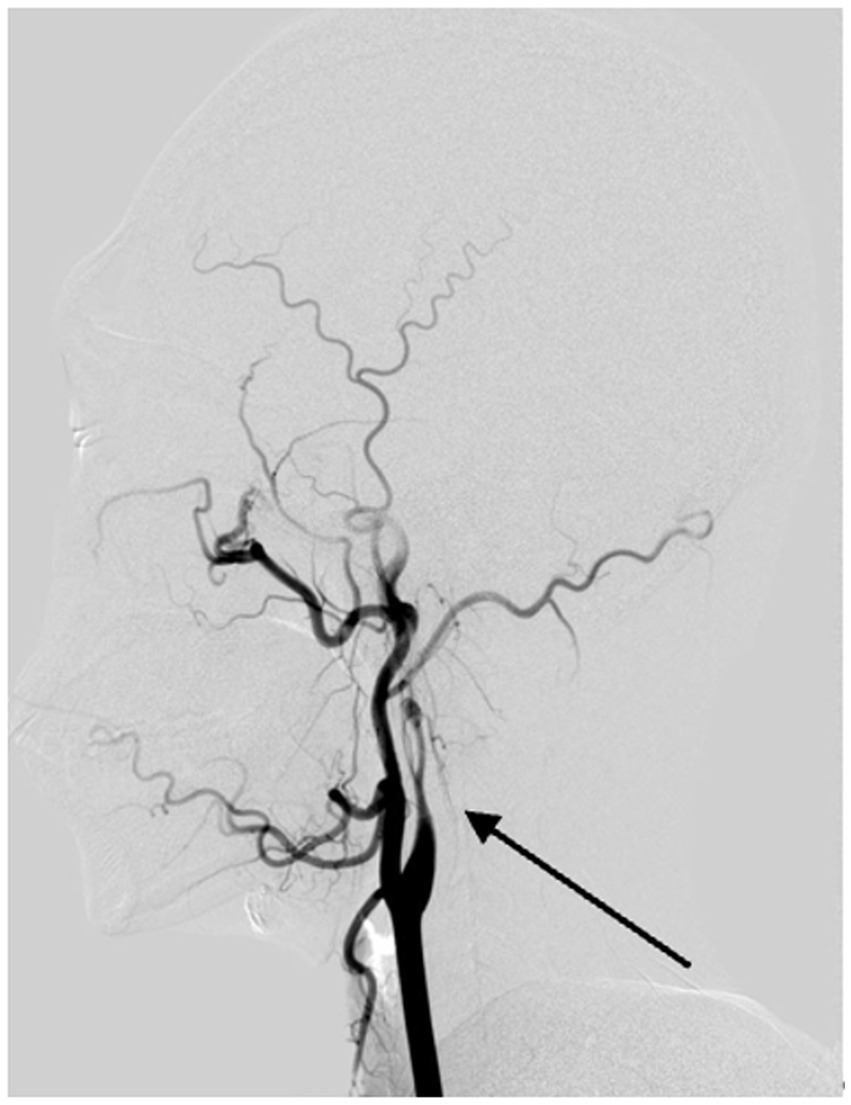

Long regarded as the gold standard for CAD diagnosis, DSA offers high spatial and temporal resolution, enabling direct visualization of luminal structures and dynamic observation of pathological vascular blood flow patterns, as well as evaluating collateral circulation and hemodynamic compensation (Figure 5). However, as an invasive procedure, DSA entails high costs, prolonged durations, and lacks assessment of vascular wall structures. In cases of subadventitial dissections without significant luminal narrowing, DSA may yield false negatives (44). Current guidelines recommend avoiding DSA as a first-line diagnostic tool, reserving it for patients with discordant MRA and CTA findings (1).

Figure 5

Digital subtraction angiography reveals vascular changes due to arterial dissection in the left internal carotid artery. The DSA image clearly demonstrates evidence of dissection in the left internal carotid artery, with the arrow pointing to a structure consistent with the 'flame sign,' characteristic of this condition.